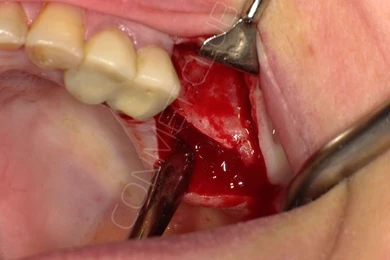

Сама же операция длиться 20-50 минут в зависимости от количества утраченных зубов. В процессе этой операции, после проведенной местной анестезии, делается разрез на слизистой, она приподнимается и субпериостальный имплантат укладывается на кость. После этого рана фиксируется несколькими швами и все! Через 10-14 дней мягкие ткани срастаются и надкостница надежно удерживает имплантат на месте. Нет необходимости ждать несколько месяцев, как это бывает в случае с внутрикостными винтовыми имплантатами.

Новые, искусственные зубы фиксируются к этому имплантату стандартными, трансокклюзионными винтами на 1-14 день (в данном клиническом случае на 5 сутки) и по существу являются несъемными!

И в-четвертых: небольшой фрагмент из операции по восстановлению всех утраченных зубов на верхней челюсти. По сути эта операция полностью повторяет протокол и этапность операции представленной в первой части статьи, за исключением того, что искусственные зубы были зафиксированы сразу после операции. Со слов самой пациентки, процесс жевания был совершенно безболезненным с самого первого дня.